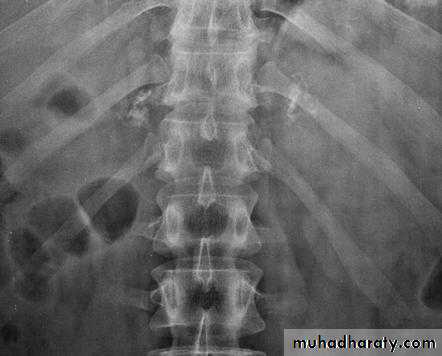

Abdominal calcifications

3. Vascular calcification: e.g. aortic aneurysm which best assessed on lateral film

11. Pancreatic calcification: occur in chronic pancreatitis & diagnosed from it's position